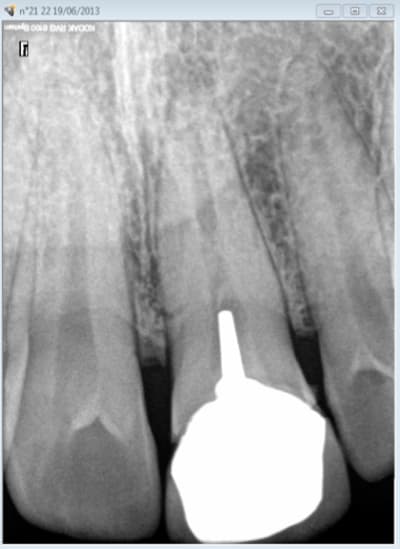

chicot29

28/02/2016 à 00h36

celle là est pas mal mais en sens inverse.De la pate avant mais plus après pose de l'ic coiffe dans le palatin.

le patient s'en est aperçu 5 ans après suite à un signe d'appel.

Ce patient c'est moi. -)

Capteur VS plaque il n'y a pas photo. -)